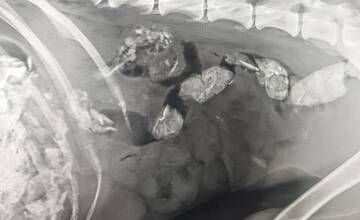

FOTO: Utýraný a vyhladovaný Odin mal v tele starší brok

FOTO: V tele týraného psíka našli brok. Previezli ho do bratislavskej Slobody zvierat